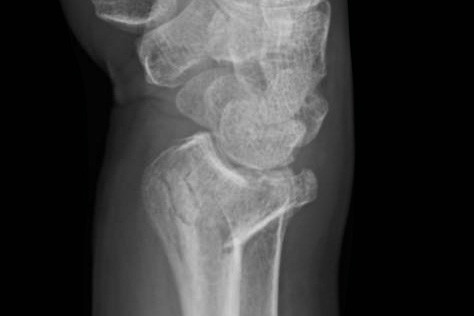

The wrist fracture. Colles fracture.